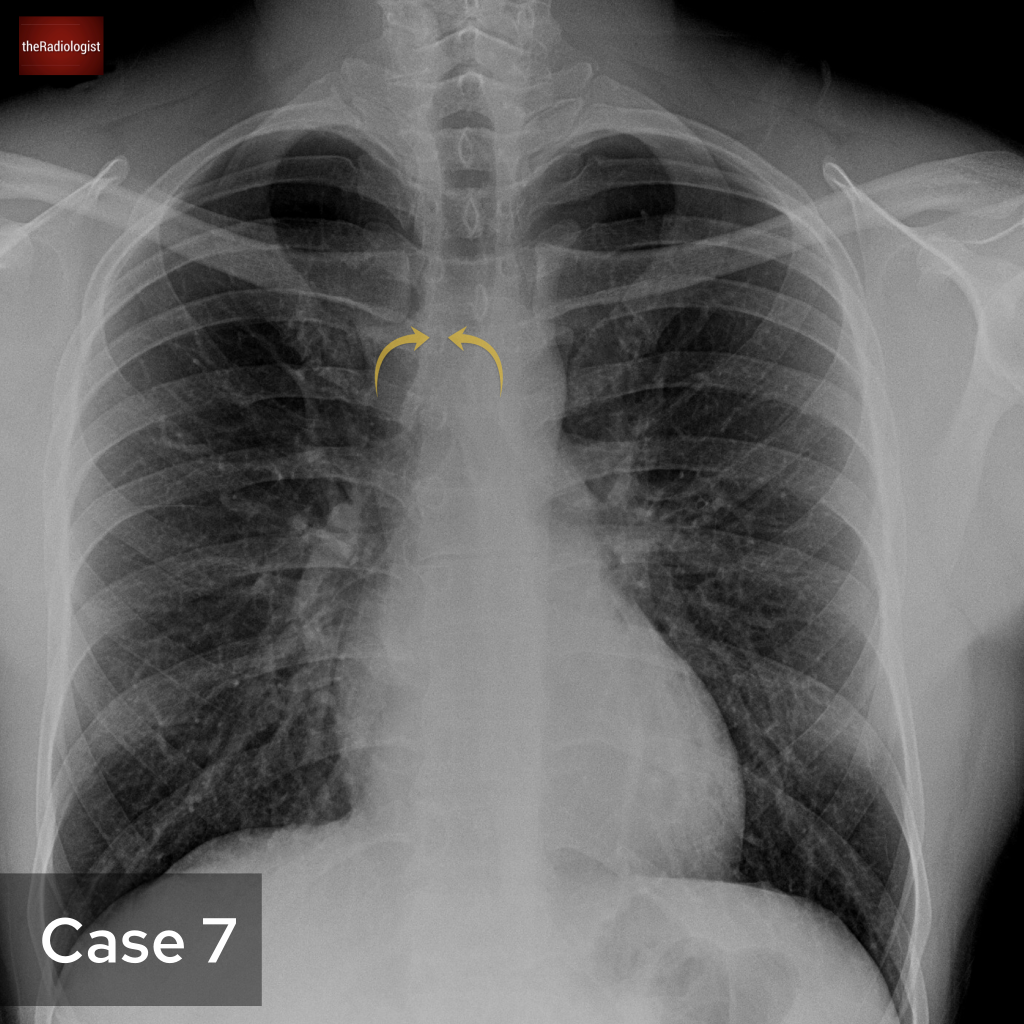

Case 7

We’ll go back to a PA chest X-Ray for this case. What are the arrows pointing at?

Choose from one of the following options: